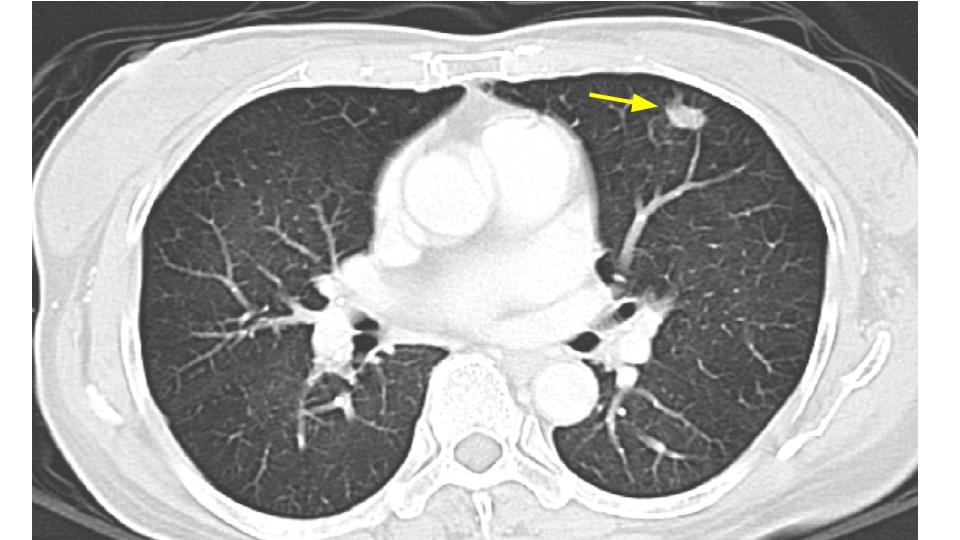

原來,這位B太太罹患的是一個 右側8.5公分腎臟腫瘤,並且可能有單一肺部轉移

針對腎臟癌的各種療法,不外乎一個原則:把原發腫瘤控制住...而最直接而且乾淨的方式就是手術切除。切除的目標是腫瘤,甚至還有腫瘤的附屬可能轉移處(如果可以切除的話),包含術中肉眼可見的淋巴結、單一的遠端肺轉移.......等。

這即是進行腎臟全切除術(減積手術, cytoreductive nephrectomy)。有整合分析研究(meta-analysis study)顯示,如果符合治療條件,再加上標靶治療(target therapy)比起單用標靶治療,對存活率是有幫忙的。前提是: 當轉移的數量是單一或者是寡量,經過評估之後是可切除的(resectable)。適合的病患族群是:大的腫瘤體積,少量的轉移目標,加上病人身體狀況不錯即可評估是否可以施行減積手術。如何預防腎臟癌?